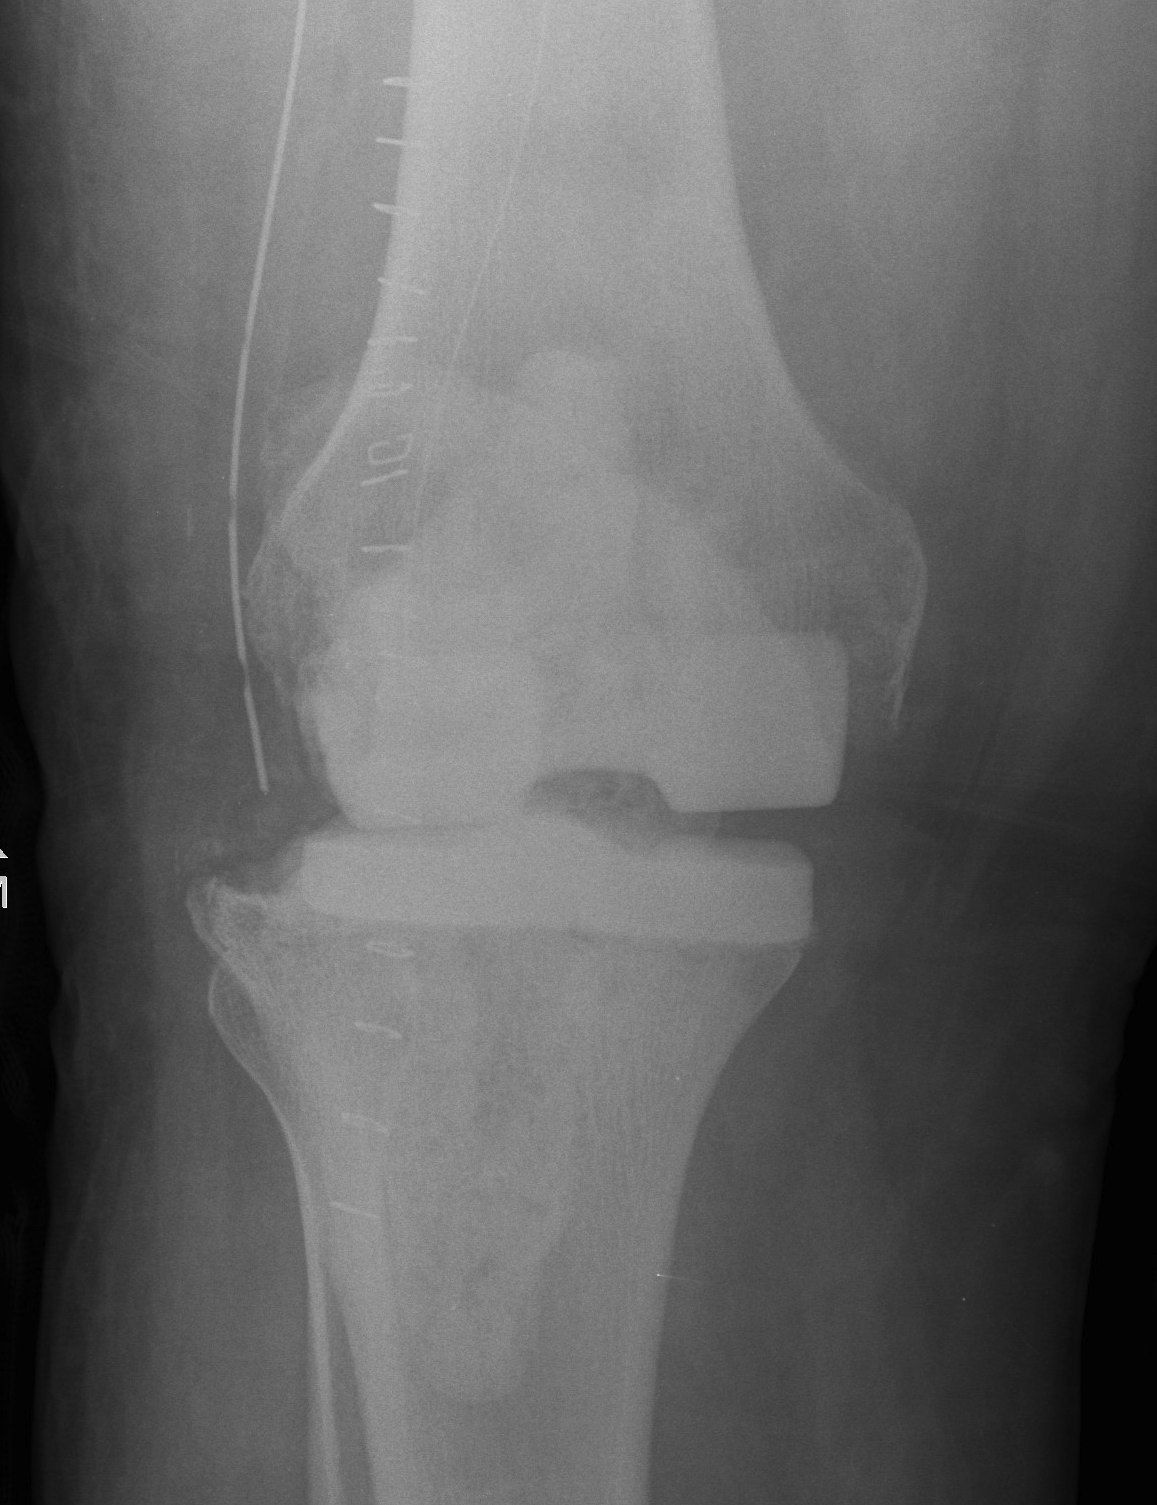

C. Femur and tibia made of antibitoic PMMA

D. Femoral implant from antibiotic cement mould / all poly tibia

Technique

- palacos cement (tobramycin) + 3G vancomycin per bag

- make femoral component from various size moulds

- cement in appropriate size all poly tibia with cement +++

- create a balanced knee

- patients are able to fully weight bear and ROM

- no rush to second stage